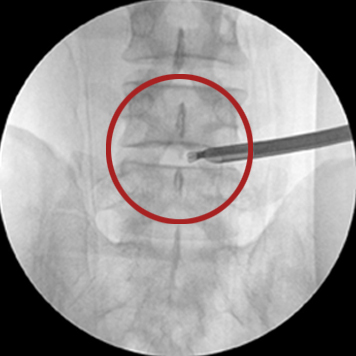

신경성형술

2mm의 초소형 카테터를 삽입하여 통증의 원인이 되는 부위를 찾아 신경 유착을 풀어주는 시술로 가장 대중적으로 사용되고 있는 척추질환 비수술치료입니다.

□ 이동식 X-ray(C-arm X-ray)로 진행 모습을 실시간으로 확인하여 안전